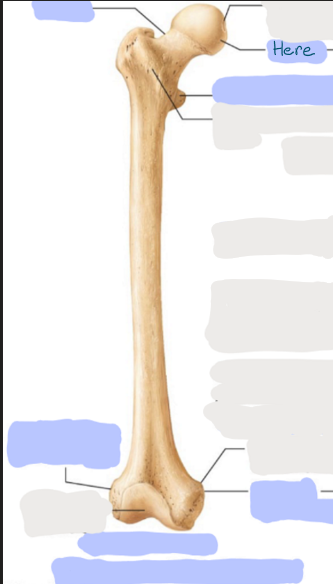

What is this picture of?

Posterior view of the Right Femur

What is here?

Where is the Head of the Femur?

What is here?

Where is the Lesser Trochanter of the Femur?

What is here?

Where is the Linea Aspera of the Femur?

What is here?

Where is the Medial Condyle of the Femur?

What is here?

Where is the Medial Epicondyle of the Femur?

What is here?

Where is the Greater Trochanter of the Femur?

What is here?

Where is the Lateral Condyle of the Femur?

What is here?

Where is the Lateral Epicondyle of the Femur?